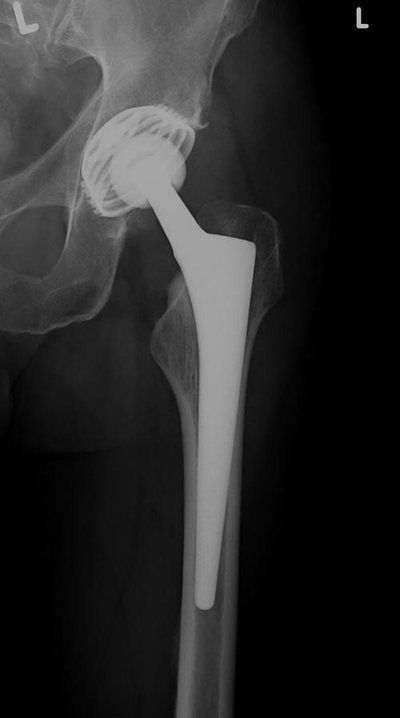

Speziell für jüngere Patienten wurden deshalb in den letzten zehn Jahren eine Reihe sogenannter Kurzschaftprothesen entwickelt. Im Gegensatz zu einer Standard-Prothese muss bei ihrem Einsatz deutlich weniger Knochen entfernt werden. Ihr Design schont die hüftübergreifende Muskulatur und die Weichteile. Dadurch ist die Rehabilitationsphase nach einer Kurzschaft-Operation meist kürzer und schmerzärmer als nach den herkömmlichen Verfahren. Berufstätigen Patienten wird ein relativ kurzfristiger Wiedereinstieg ins Arbeitsleben möglich. „Wenn sich diese Kurzschaftprothese nach 15 bis 20 Jahren gelockert haben sollte, kann sie in der Regel noch durch eine Standard-Prothese ersetzt werden“, weist der Chefarzt auf einen entscheidenden Vorteil hin.

Aber auch ältere Patienten können bis etwa zum 70. Lebensjahr durchaus mit einer Kurzschaftprothese versorgt werden, wenn ihre Knochenqualität im hüftgelenksnahen Oberschenkelbereich es zulässt. Die Entscheidung, welcher Endoprothesentyp zum Einsatz kommt, wird von Fall zu Fall neu geprüft werden. Die computergestützte OP-Planung orientiert sich an einem Röntgenbild des Hüftgelenkes in zwei Ebenen. „Da wir seit einiger Zeit die Versorgung unserer jüngeren Patienten in unserer Klinik mit Kurzschaftprothesen durchführen, werden wir die Operationsergebnisse am Ende des Jahres wissenschaftlich auswerten und daraus Rückschlüsse für unser Qualitätsmanagement ziehen“, so Dr. Rimkus.